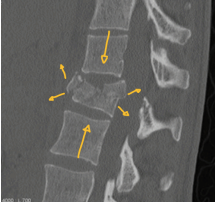

Espondilolise

* Fratura da região entre os processos articulares da vértebra (pars inter-articularis)

* Melhor visibilizada na radiografia [—]

A

obliqua